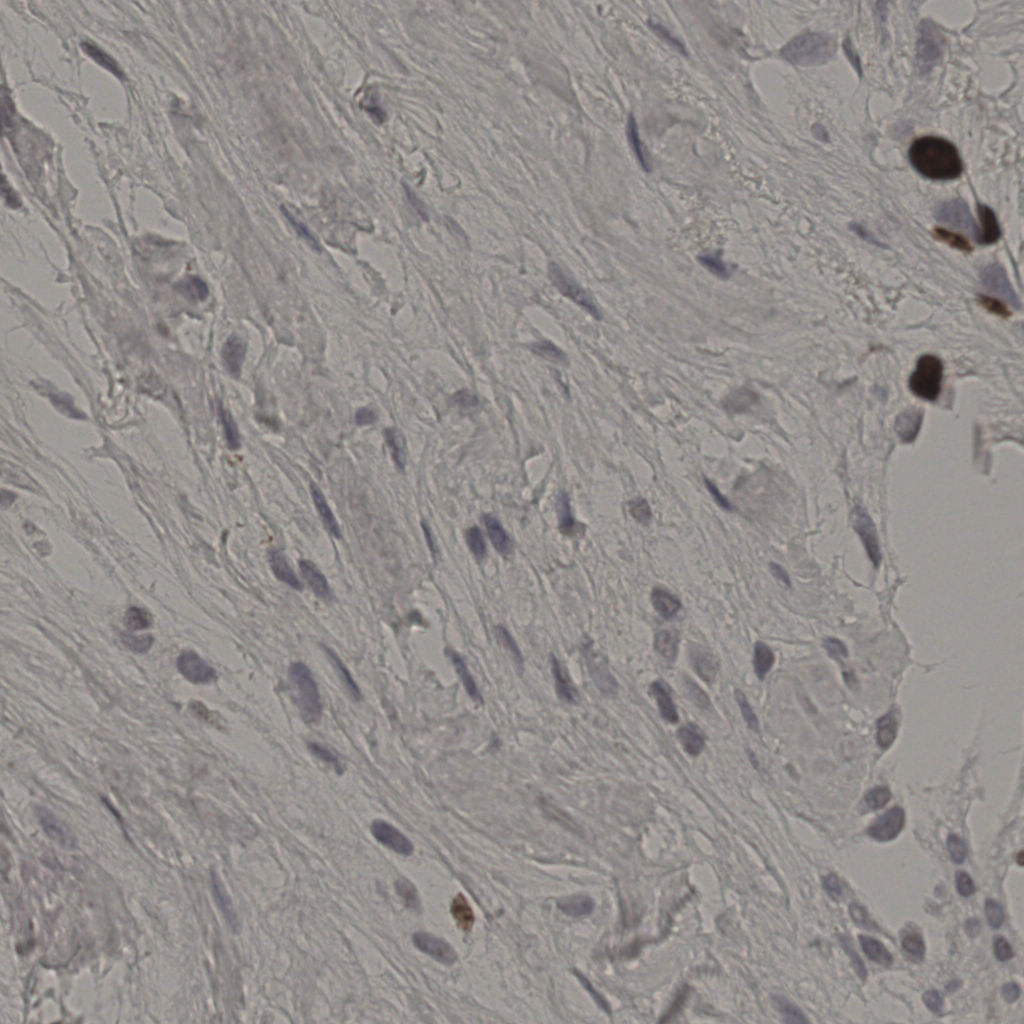

缩略图

标记后

标记前